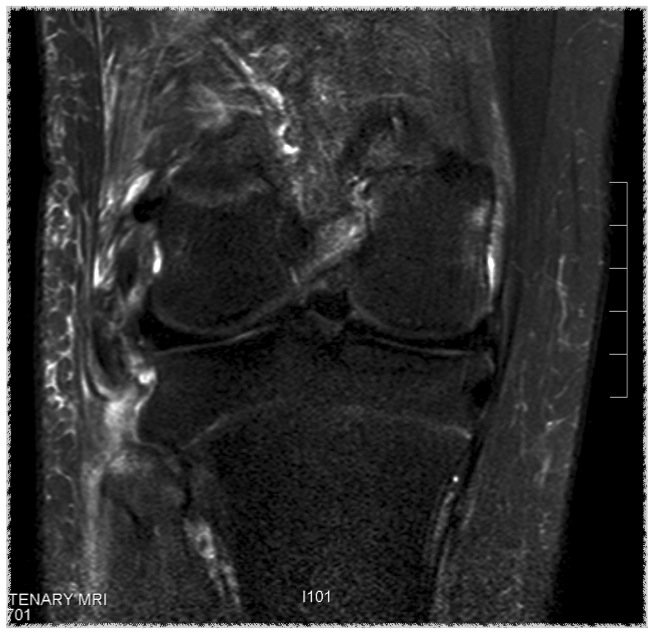

MRI

Chronic distal avulsion LCL

Sagittal MRI showing torn ACL Coronal MRI demonstrating chronic avulsion LCL fibula head